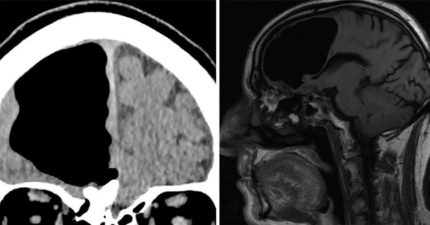

男子被驗出「巨大腦洞」,「半個大腦不見了」但仍跟我們一樣正常!醫生這樣解釋